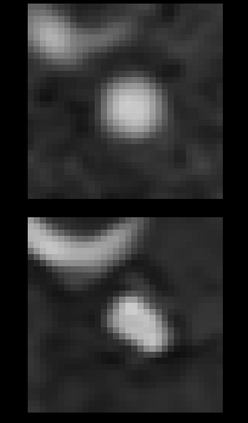

We hereby present a full synthetic model, able to mimic the various constituents of the cerebral vascular tree: the cerebral arteries, the bifurcations and the intracranial aneurysms. By building this model, our goal was to provide a substantial dataset of brain arteries which could be used by a 3D Convolutional Neural Network (CNN) to either segment or detect/recognize various vascular diseases (such as artery dissection/thrombosis) or even some portions of the cerebral vasculature, such as the bifurcations or aneurysms. In this study, we will particularly focus on Intra-Cranial Aneurysm (ICA) detection and segmentation. The cerebral aneurysms most often occur on a particular structure of the vascular tree named the Circle of Willis. Various studies have been conducted to detect and monitor the ICAs and those based on Deep Learning (DL) achieve the best performances. Specifically, in this work, we propose a full synthetic 3D model able to mimic the brain vasculature as acquired by Magnetic Resonance Angiography (MRA), and more particularly the Time Of Flight (TOF) principle. Among the various MRI modalities, the MRA-TOF allows to have a relatively good rendering of the blood vessels and is non-invasive (no contrast liquid injection). Our model has been designed to simultaneously mimic the arteries geometry, the ICA shape and the background noise. The geometry of the vascular tree is modeled thanks to an interpolation with 3D Spline functions, and the statistical properties of the background MRI noise is collected from MRA acquisitions and reproduced within the model. In this work, we thoroughly describe the synthetic vasculature model, we build up a neural network designed for ICA segmentation and detection, and finally, we carry out an in-depth evaluation of the performance gap gained thanks to the synthetic model data augmentation.